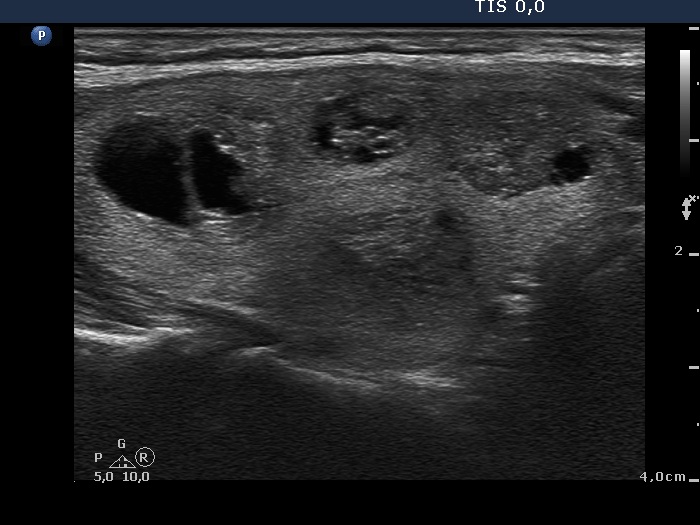

Ultrasonography. The thyroid was echonormal and contained numerous nodules with different echogenicities.

Cytology was performed from two lesions located in the right lobe and resulted in benign colloid goiter and in benign cystic-colloid goiter, nodule in the middle-dorsal part and in the lower pole, respectively.